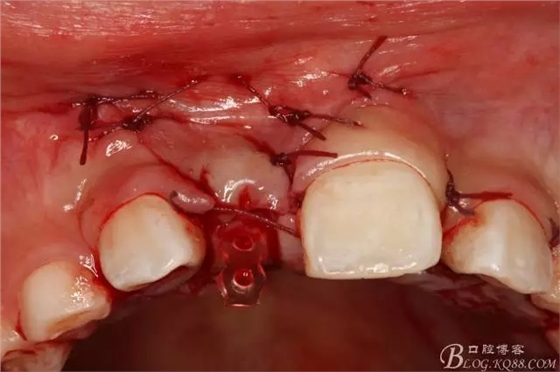

圖11.光固化粘結(jié)托槽于11的舌面。

圖12.粘結(jié)完畢的托槽。

圖13.縫合唇側(cè)切口及腭側(cè)切口。